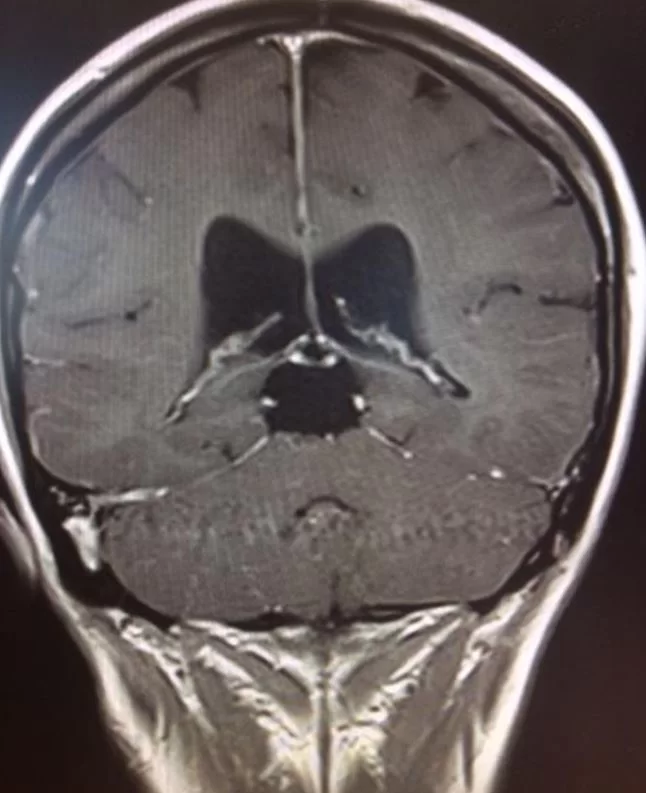

Ο απεικονιστικός έλεγχος με μαγνητική τομογραφία ανέδειξε ευμεγέθη όγκο στην περιοχή της επίφυσης (κωνάριο), καθώς επίσης και διάταση του κοιλιακού συστήματος (υδροκέφαλο)